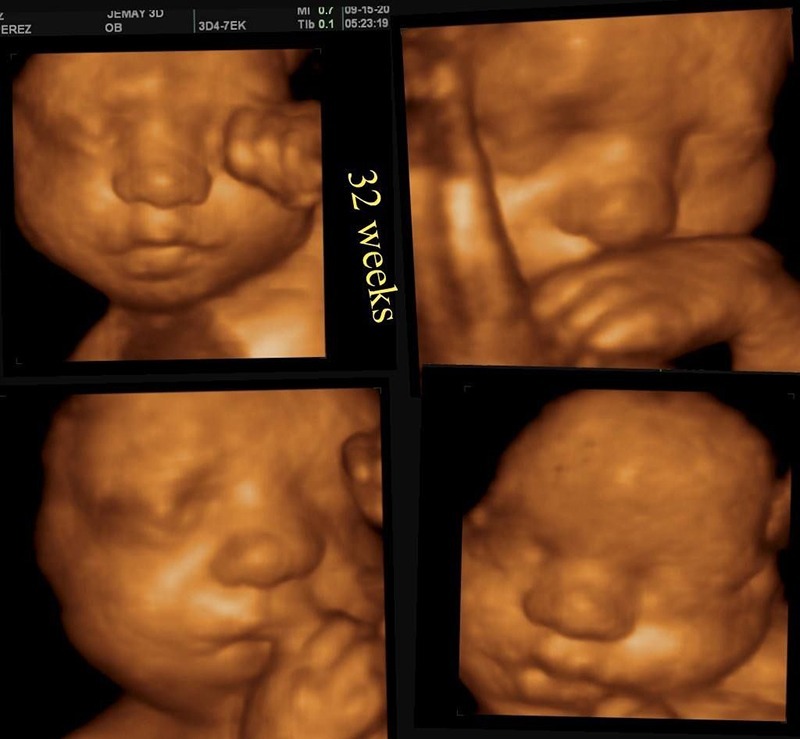

Siêu âm 4D là gì?

Siêu âm 4D là phiên bản nâng cấp của siêu âm 3D, cho phép hiển thị hình ảnh chuyển động theo thời gian thực, giống như một đoạn video trực tiếp. Nhờ đó, người xem có thể thấy được cử động của thai nhi như mỉm cười, ngáp hay cử động tay chân. Siêu âm 4D thường được sử dụng trong thai kỳ để tạo trải nghiệm sinh động cho cha mẹ và hỗ trợ phát hiện bất thường sớm.

Đặc điểm nổi bật của siêu âm 4D:

- Hình ảnh ba chiều kết hợp chuyển động theo thời gian thực.

- Cho phép quan sát cử động sống động của thai nhi.

- Tăng tính tương tác và cảm xúc cho cha mẹ khi theo dõi.

- Thiết bị hiện đại, chi phí cao hơn các loại siêu âm khác.